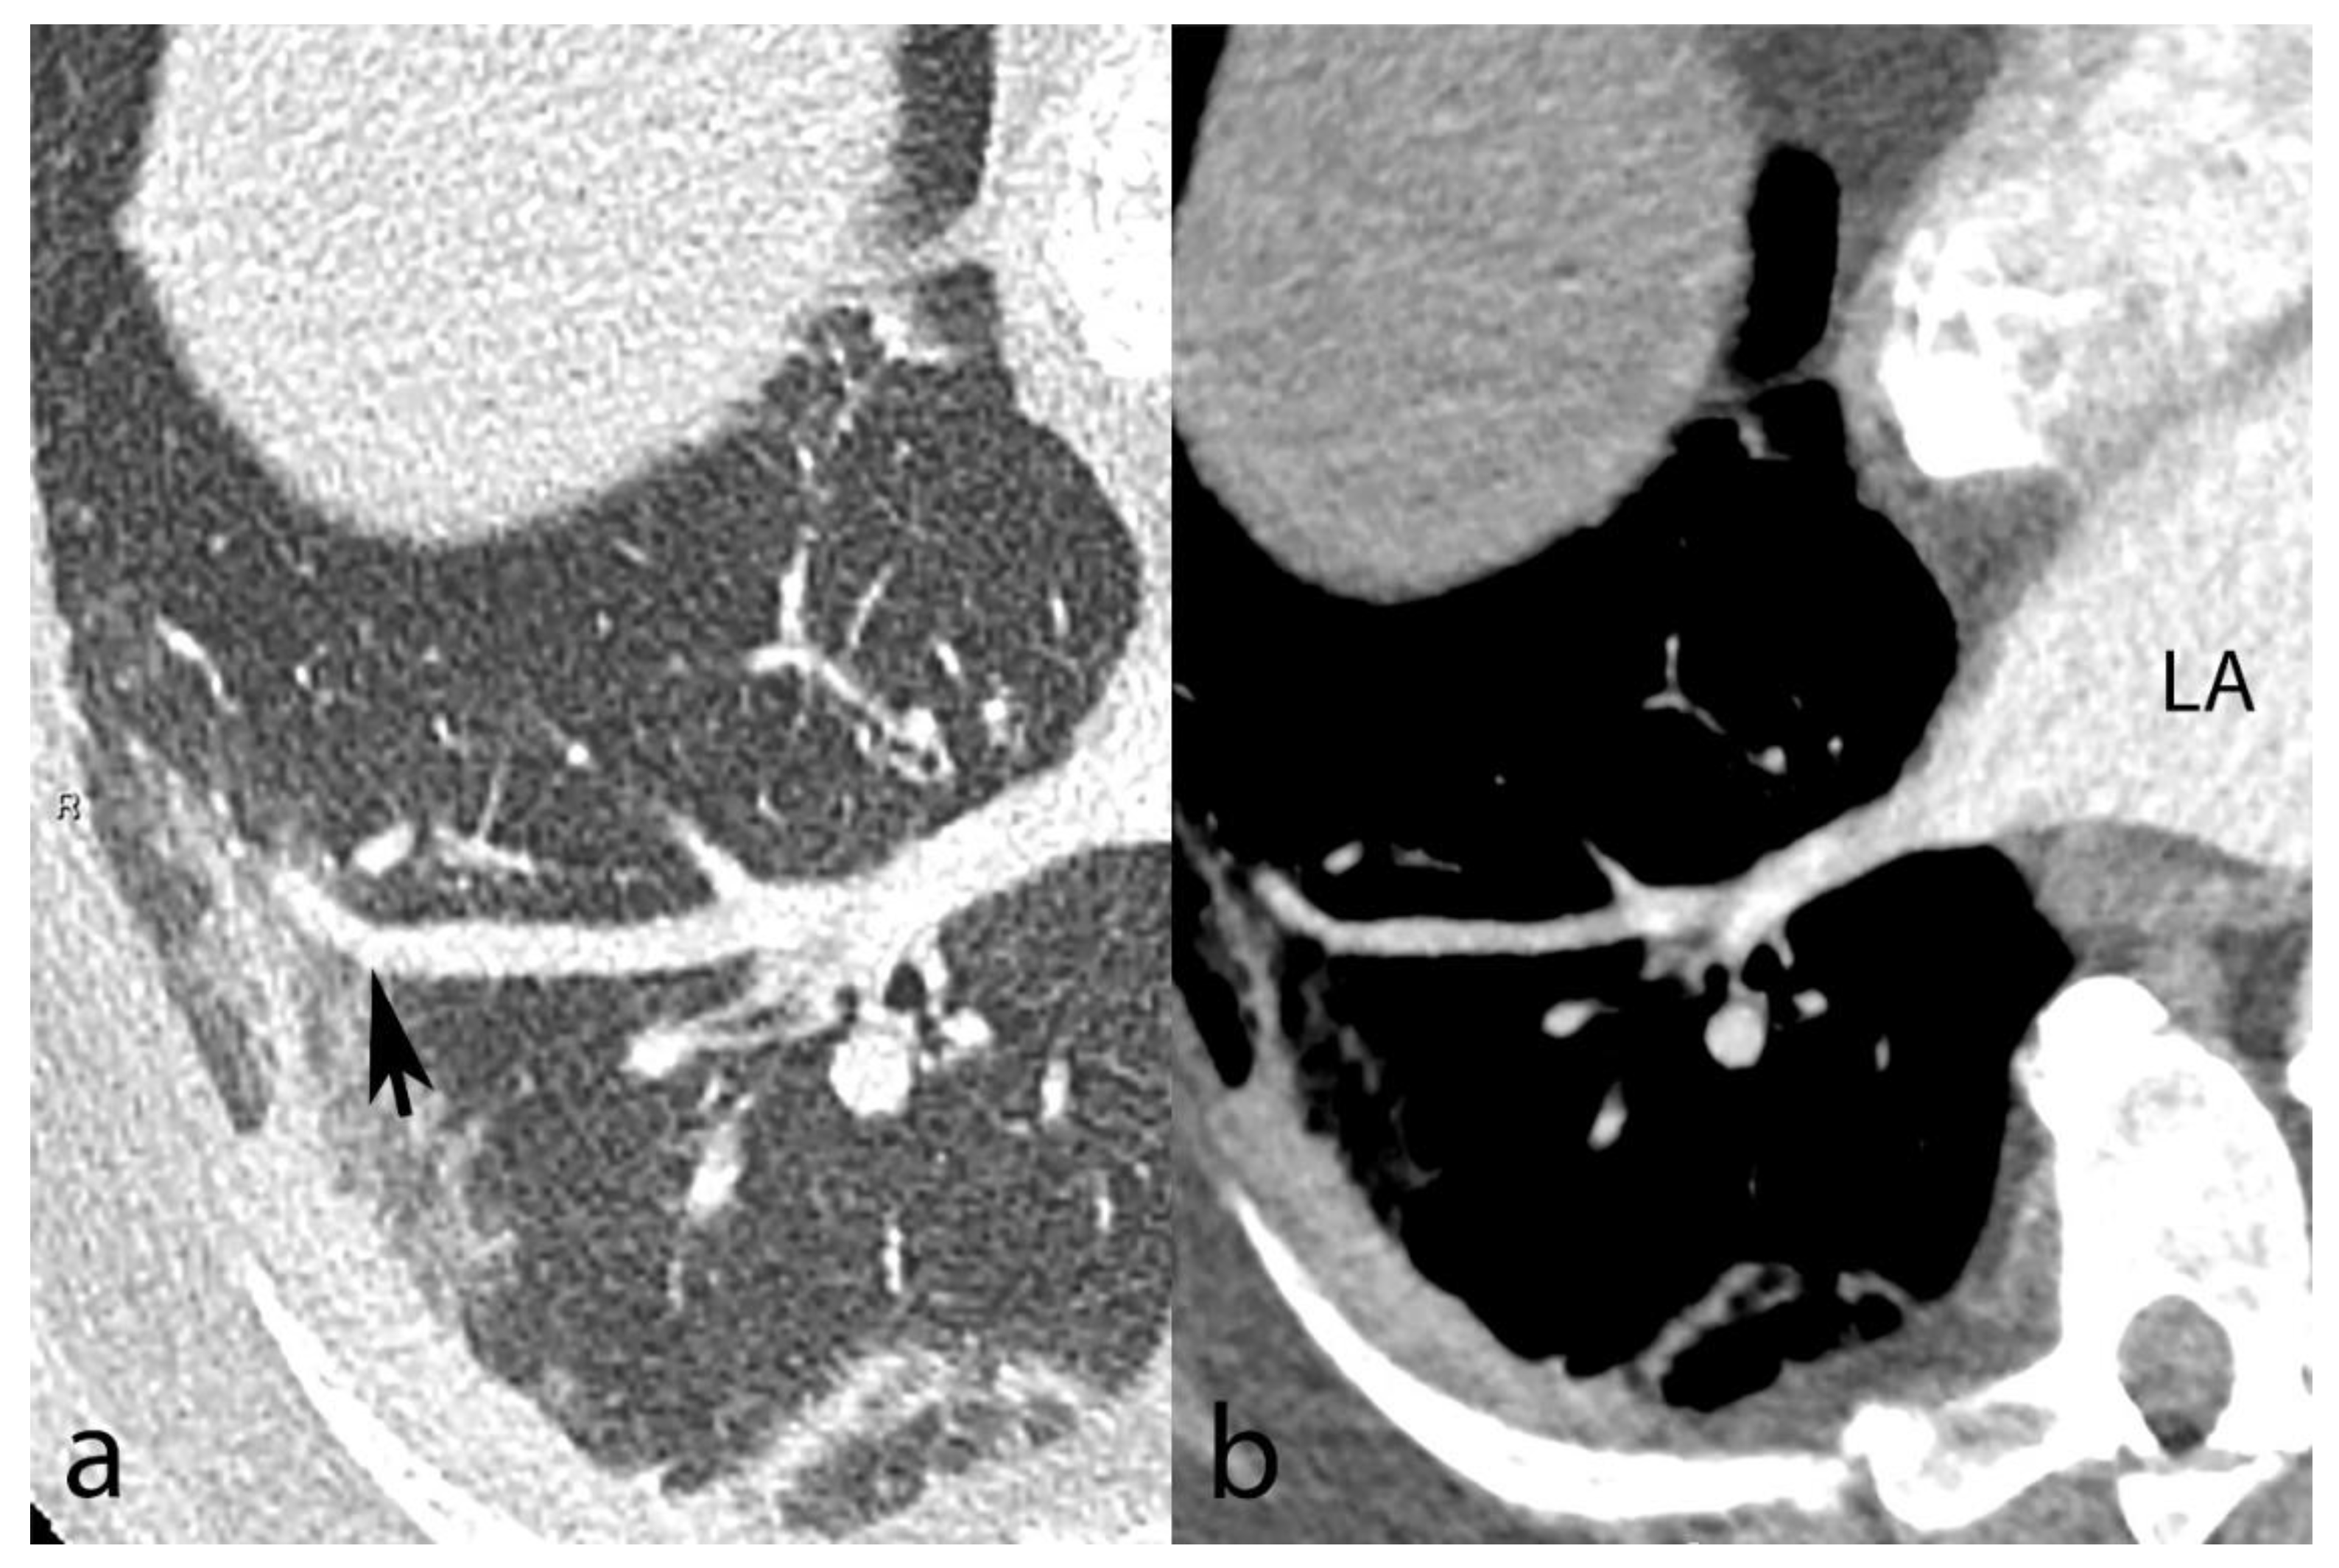

Figure 3.

Contrast-enhanced chest CT from a 67-year-old male shows SARS-CoV-2 pneumonia with mixed peripheral ground-glass opacities and consolidation in the right lower lobe. Venous congestion is seen in the apical segment (panel (a), black arrow). A reformatted oblique axial image with mediastinal window settings (panel (b)) demonstrates the venous nature of the dilated vessel based on its connection to the left atrium (LA).